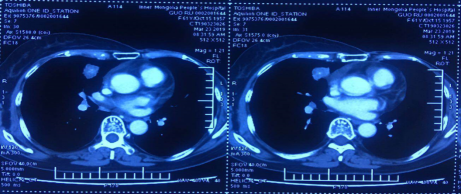

2018年12月,疾病再次进展。转移灶大小:25×27mm。

右肺中叶内侧段结节25×27mm,较前增大纵膈、右肺门多发增大淋巴结

根据2018版CSCO BC指南及PALOMA3研究数据,患者二线治疗:哌柏西利+氟维司群,具体用法:氟维司群:500mg,im,d1、14、28,之后每28 d一次。哌柏西利:125mg起始,3周休1周。前两周期d1、d15、d21d定期复查血象。

疗效评价:PR。转移灶大小:22×24mm